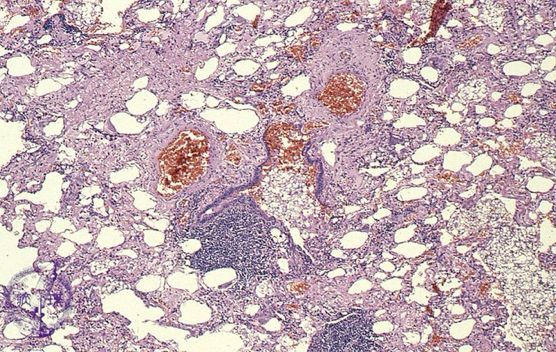

"But, that right focal consolidation and contralateral tiny nodules bother me though… *lepidic/muc adeno alert*"

Indeed!

Surgical Lung Biopsy: Diffuse adenocarcinoma with areas of lepidic growth.